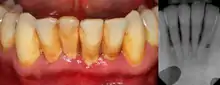

![]() | |

| Gingival enlargement can be a feature in some periodontal diseases. | |